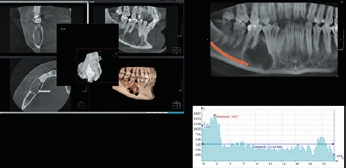

- Die digitale Volumentomographie (DVT) liefert die höchste Auflösung von knöchernen Strukturen, die Darstellung und/oder Differenzierung von Weichgewebe ist jedoch nicht möglich. Vorteile sind die geringen Kosten und die im Vergleich zur CT reduzierten Metallartefakte. Nachteilig hingegen sind der geringe Weichteilkontrast und die Gewebedifferenzierung (Abb. 2 u. 3).

Durch weitere Rechenprozesse können die Daten auf verschiedenste Weise dargestellt werden. Die multiplanaren Rekonstruktionen (MPR) stellen die sinnigste Weiterverarbeitung der Daten dar. Hierbei wird das Volumen durch senkrecht zueinander stehende Ebenen zerlegt, wodurch die Ansichten axial, sagittal und koronal erzeugt werden, ergänzt durch die oberflächengerenderte Ansicht (Abb. 9). Das Angebot entsprechender Bildbearbeitungsprogramme ist vielfältig, zumeist wird das DVT-Gerät mit einer adäquaten Software installiert und eingerichtet – ab diesem Zeitpunkt ist nun der/die Anwender/-in gefordert. In Deutschland ist die Absolvierung eines DVT-Kurses vor Inbetriebnahme eines DVT-Gerätes gesetzlich vorgeschrieben.